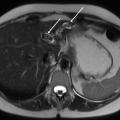

La cholangiographie par IRM est typiquement normale dans les formes habituelles, microlithiasiques, du syndrome LPAC. Elle n’est donc pas nécessaire au diagnostic dans la très grande majorité des situations. Elle doit être réalisée en cas de calculs intrahépatiques ou de dilatation des canaux biliaires en échographie afin d’évaluer le retentissement de ces calculs sur les voies biliaires et le parenchyme hépatique. Les calculs biliaires ne sont pas toujours visibles à l’imagerie par résonance magnétique (IRM), notamment quand leur taille est inférieure à 5 mm. Lorsqu’ils sont visibles, ils sont le plus souvent visualisés en hyposignal T1 et T2 sous forme de lacunes endobiliaires (fig. 2 A et 2B). Dans une série récente portant sur 125 patients suivis dans un centre expert et ayant tous eu une bili-IRM, 49 % présentaient des anomalies des canaux biliaires, parmi lesquelles 93 % de calculs intra­hépatiques et 38 % de dilatation des canaux biliaires.10 Ces anomalies morphologiques étaient plus fréquemment observées chez les porteurs d’un variant pathogène du gène ABCB4.